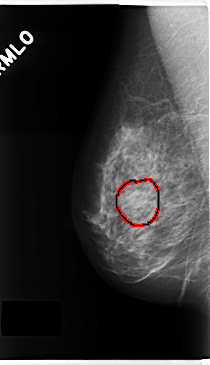

FILE: C_0229_1.RIGHT_MLO.OVERLAY

TOTAL_ABNORMALITIES 1

ABNORMALITY 1

LESION_TYPE MASS SHAPE OVAL MARGINS CIRCUMSCRIBED

ASSESSMENT 3

SUBTLETY 5

PATHOLOGY BENIGN

TOTAL_OUTLINES 1

BOUNDARY